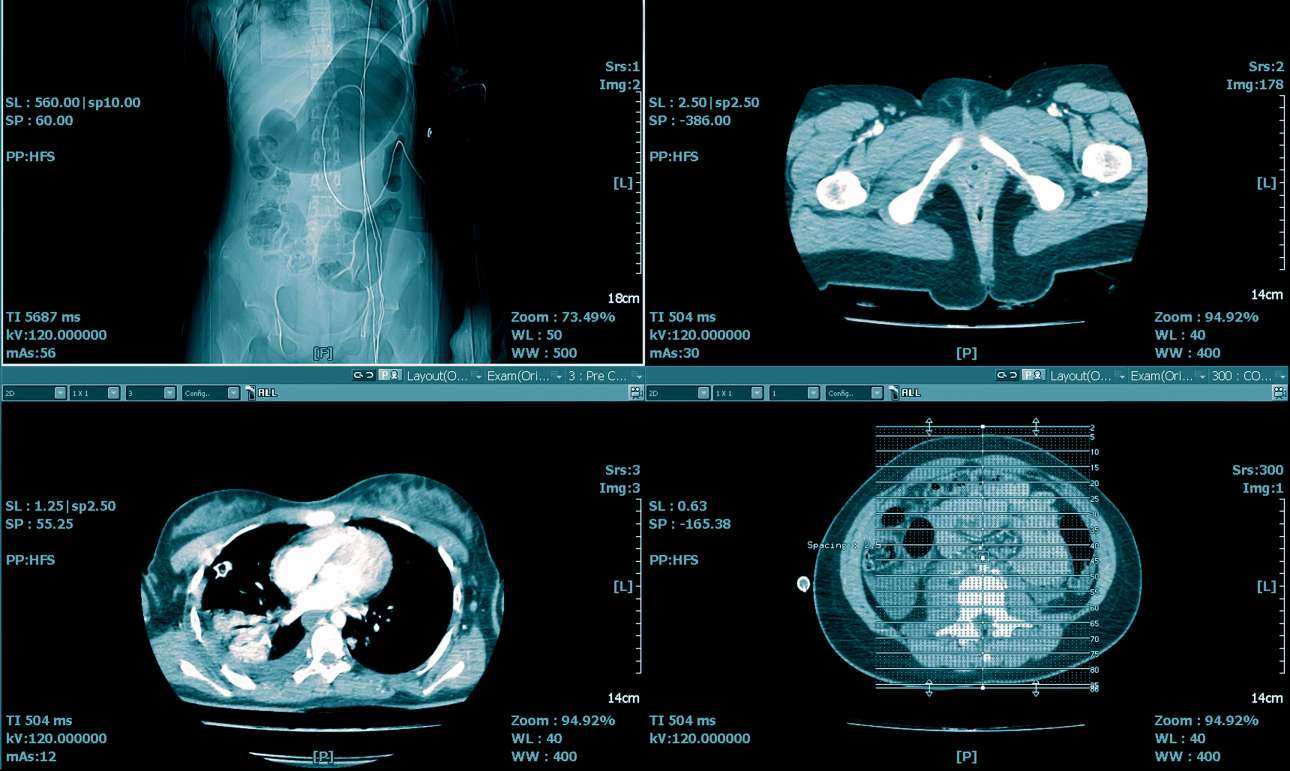

Ενα σπάνιο είδος καρκίνου για το οποίο η ΤΝ προσφέρει λεπτομερέστατες πληροφορίες είναι τα σαρκώματα στη κοιλιακή χώρα, που προκαλούν έντονους στομαχικούς πόνους. Μέχρι πρόσφατα οι γιατροί εντόπιζαν την ύπαρξή τους μέσω αξονικών τομογραφιών. Σήμερα, η χρήση προγραμμάτων ΤΝ προσφέρει περισσότερα δεδομένα για την αφαίρεση του καρκινώματος από την απλή βιοψία με βελόνα, η οποία είναι και αρκετά επισφαλής.

Οι ερευνητές, που δημοσίευσαν τα πορίσματά τους στο ιατρικό περιοδικό Lancet Oncology, χρησιμοποίησαν μια τεχνική που ονομάζεται «ραδιομική ανάλυση εικόνας» για να εντοπίσουν σημεία, αόρατα με γυμνό μάτι, του οπισθοπεριτοναϊκού σαρκώματος –το οποίο αναπτύσσεται στον συνδετικό ιστό του πίσω μέρους της κοιλιακής χώρας– σε τομογραφίες 170 ασθενών.

Με αυτά τα δεδομένα, ο αλγόριθμος ΤΝ κατάφερε να βαθμολογήσει την επιθετικότητα 89 άλλων όγκων σε νοσοκομειακούς ασθενείς στην Ευρώπη και στις ΗΠΑ, από σαρώσεις τομογράφων, με πολύ μεγαλύτερη ακρίβεια από τις βιοψίες, κατά τις οποίες ένα μικρό μέρος του καρκινικού ιστού αναλύεται στο μικροσκόπιο.

Σύμφωνα με μια νέα μελέτη, η ΤΝ προσφέρει διπλάσιες δυνατότητες εντοπισμού της επιθετικότητας σπάνιων μορφών καρκίνου εν συγκρίσει με τις συμβατικές υφιστάμενες. Αναγνωρίζοντας λεπτομέρειες αόρατες με γυμνό μάτι στις σαρώσεις τομογράφων, η τεχνολογία έχει ακρίβεια επιπέδου 82%, σε σύγκριση με το 44% της συμβατικής εργαστηριακής ανάλυσης.